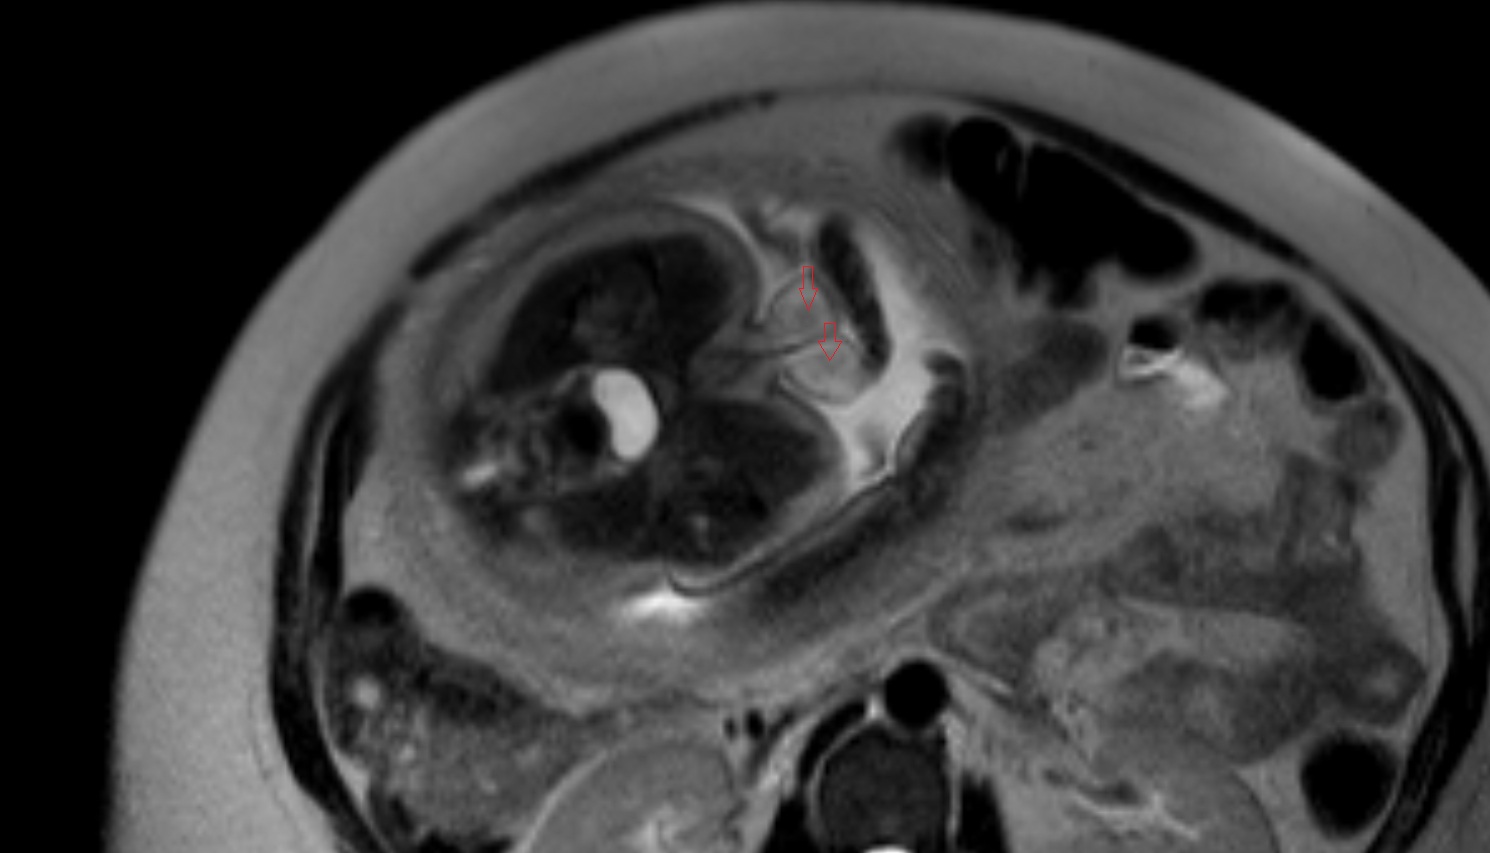

- Fetal brain

- Fetal caudate nucleus

- Fetal thalamus

- Fetal pons

- Fetal cerebellum

- Fetal occipital lobe

- Fetal temporal lobe

- Fetal parietal lobe

- Fetal frontal lobe

- Fetal third ventricle

- Fetal fourth ventricle

- Fetal lateral ventricle